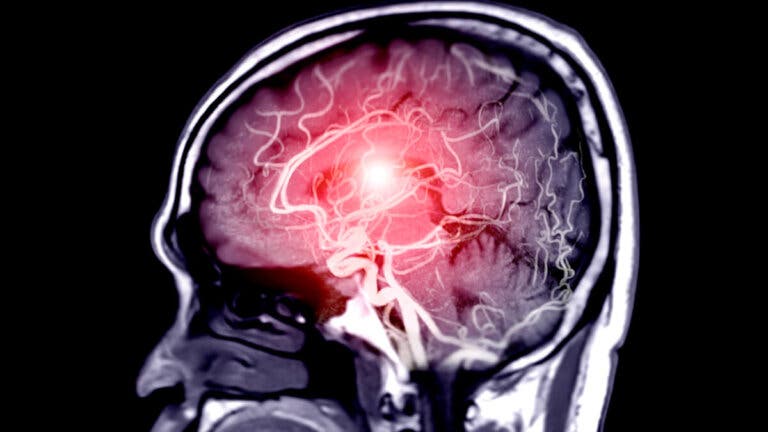

Un aneurisma es un ensanchamiento anormal de una arteria causado por la debilidad en la pared de un vaso sanguíneo. Esta anomalía afecta más a las mujeres después de los 50 años. Conoce en este artículo cómo detectar y prevenir aneurismas.

En el caso del aneurisma cerebral, puede expandirse sin llegar a reventar, presionar los nervios y provocar dolor de cabeza, visión doble y vértigo, así como también zumbido en los oídos, pérdida de la orientación, rigidez en el cuello, no poder articular palabras, no entender cuando se le habla a la persona afectada, sensibilidad a la luz, vómitos, convulsiones o pérdida de conocimiento.

Cerca del 5 % de la población padece aneurisma cerebral, y quienes tienen más riesgo de padecer este problema son aquellos con antecedentes familiares o con problemas de circulación sanguínea. También son propensos a padecerlos los fumadores, consumidores de alcohol y drogas o incluso cualquier persona de edad avanzada.